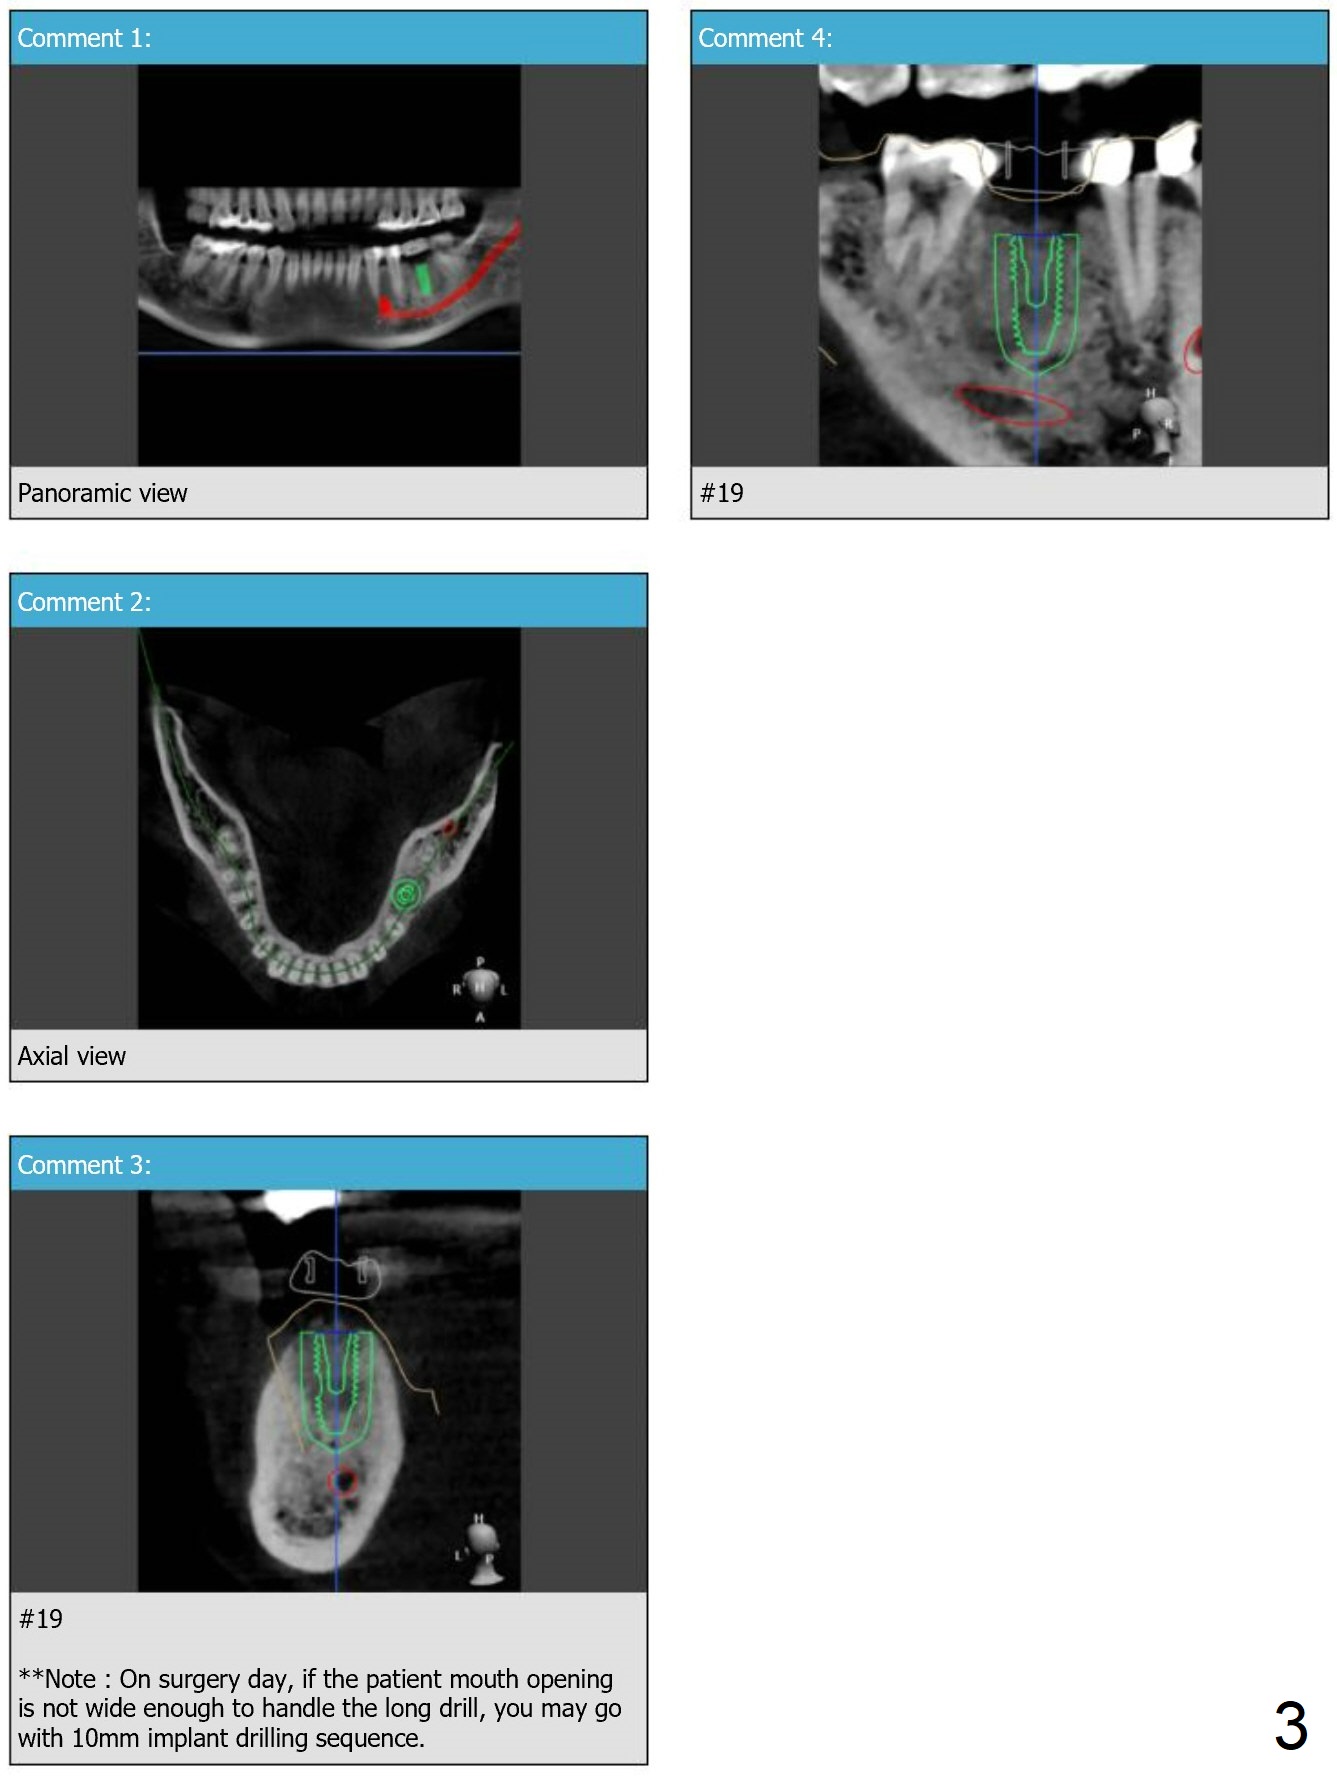

Implant Length/Mouth Opening

Although the woman is short, her bone at #19 is long enough for 11.5 mm implant (Fig.5). If her mouth opening is limited, the last drill will be 10 mm (Fig.6).